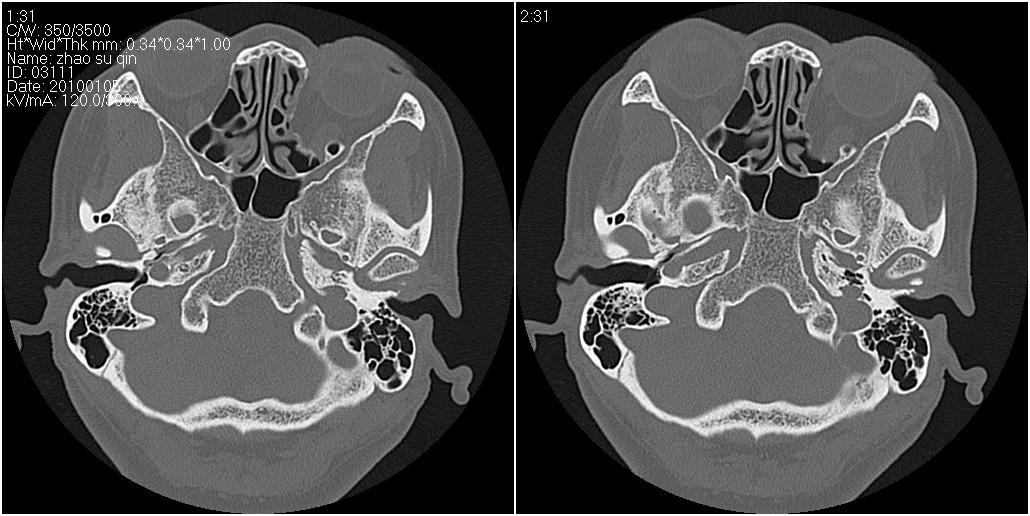

标题: CT24015:一个头部外伤患者进行鉴定,除了左侧筛板骨折,哪 [打印本页]

标题: CT24015:一个头部外伤患者进行鉴定,除了左侧筛板骨折,哪

看了几遍,其余未见明显骨折征。

左眶下裂部好像有骨折 似有小碎骨片

1)左侧筛板骨折。2)双侧筛窦炎症(或积血)。

其余未见明显骨折征。

请明示骨折部位。